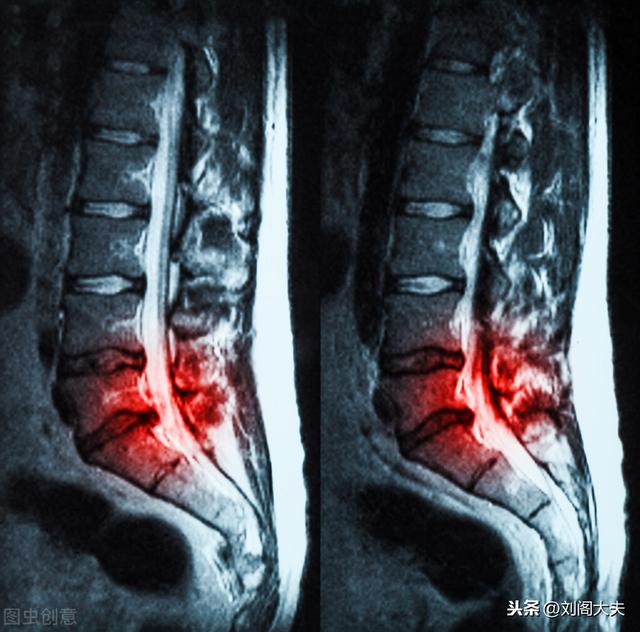

Hernie discale lombaire Qu'est-ce que l'hernie discale lombaire ? Nous savons tous que les os s'empilent pour former notre colonne vertébrale, mais nous ne pouvons pas laisser l'os broyer l'os ah, alors l'évolution humaine a joint le disque à ce coussin souple, mais les êtres humains travaillent souvent en portant le poids de l'usure, avec le temps ce coussin souple du disque s'épuisera de la compression des tissus et des nerfs correspondants apparaîtra des symptômes pathologiques correspondants, tels que le lumbago, la douleur de la jambe, l'engourdissement de la jambe, le bois de la jambe, la gêne sérieuse dans les intestins, la compression du nerf sciatique apparaîtra des symptômes de la jambe. Douleur dans les jambes, engourdissement des jambes, bois dans les jambes, gêne urinaire et fécale grave, la compression du nerf sciatique se traduira par des symptômes dans les jambes.

La hernie discale intervertébrale lombaire est l'une des maladies les plus courantes, principalement en raison des parties du disque intervertébral lombaire, notamment le nucleus pulposus, l'anneau fibreux et la plaque cartilagineuse, en particulier le nucleus pulposus, qui subit des changements dégénératifs plus ou moins importants sous l'effet de facteurs externes, l'anneau fibreux du disque intervertébral se rompt, le tissu du nucleus pulposus fait saillie à l'endroit de la rupture ou se prolonge dans la partie postérieure ou dans le canal vertébral. Le nucleus pulposus fait saillie ou se détache de la zone de rupture vers le dos ou le canal vertébral, provoquant l'irritation ou la compression des racines nerveuses spinales adjacentes, produisant ainsi une série de symptômes cliniques tels que la douleur lombaire, l'engourdissement et la douleur dans un ou les deux membres inférieurs. L'incidence de la hernie discale lombaire est la plus élevée dans les lombaires 4-5 et les lombaires 5-sacrées 1, soit environ 95 %.